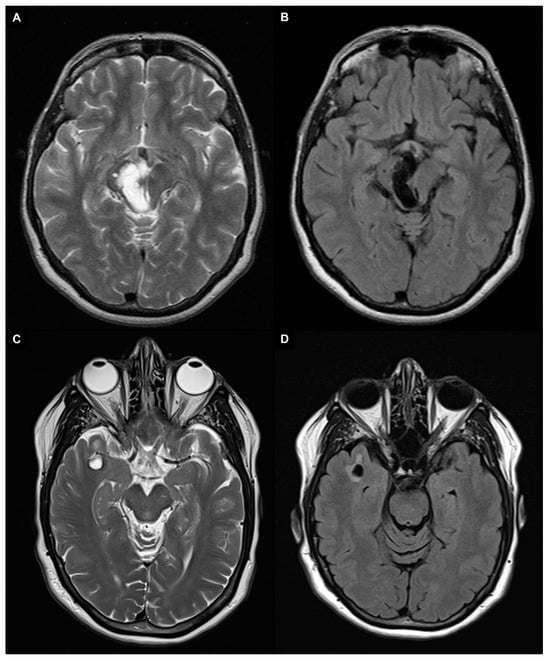

- Wardlaw, J.M.; Smith, E.E.; Biessels, G.J.; Cordonnier, C.; Fazekas, F.; Frayne, R.; Lindley, R.I.; O’Brien, J.T.; Barkhof, F.; Benavente, O.R.; et al. Neuroimaging Standards for Research into Small Vessel Disease and Its Contribution to Ageing and Neurodegeneration. Lancet Neurol. 2013, 12, 822–838. [Google Scholar] [CrossRef]

- Kwee, R.M.; Kwee, T.C. Virchow-Robin Spaces at MR Imaging. Radiogr. Rev. Publ. Radiol. Soc. N. Am. Inc. 2007, 27, 1071–1086. [Google Scholar] [CrossRef]

- Rudie, J.D.; Rauschecker, A.M.; Nabavizadeh, S.A.; Mohan, S. Neuroimaging of Dilated Perivascular Spaces: From Benign and Pathologic Causes to Mimics. J. Neuroimaging Off. J. Am. Soc. Neuroimaging 2018, 28, 139–149. [Google Scholar] [CrossRef] [PubMed]

- Kwee, R.M.; Kwee, T.C. Tumefactive Virchow-Robin Spaces. Eur. J. Radiol. 2019, 111, 21–33. [Google Scholar] [CrossRef] [PubMed]

| FLAIR | ↓↓ | ↑↑ | ↓↓ with ↑ rim | ↑↑ | ↓↓ with ↑ rim | ↓↓ (↑ in neurenteric cysts) | ↑↑with possible ↑ rim | ↓↓ with ↑ rim | Variable | ↓↓ with ↑ rim |

| T2 | ↑↑ | ↑↑ | ↑↑ | ↑ | ↑↑ | ↑↑ | ↑/↑↑ | ↑↑ | Variable | ↑↑ |

| T1 | ↓↓ | ↓↓ | ↓↓ | ↓ | ↓↓ | ↓↓ (↑ in neurenteric cysts) | ↓/↓↓ | ↓↓ | Variable | ↓↓ |